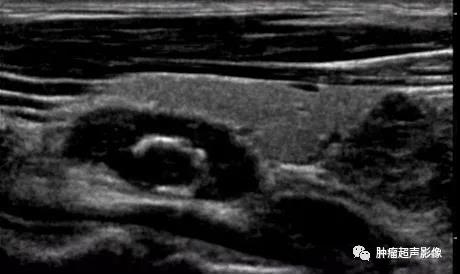

慢性肾脏疾病,血PTH升高,左侧2个(上图)、右侧1个(下图)增大的甲状旁腺腺体,呈边界清的低回声,与甲状腺分界清晰,其中两个内见钙化。